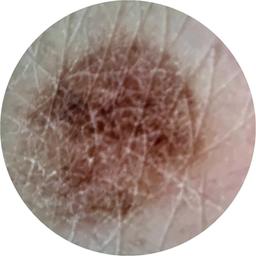

MEL-SELF - Dermoscopic

- Name: MEL-SELF - Dermoscopic

Dermoscopic lesion images (close-up views of benign and malignant lesions) from the MEL-SELF trial (the Melanoma Self Surveillance trial).